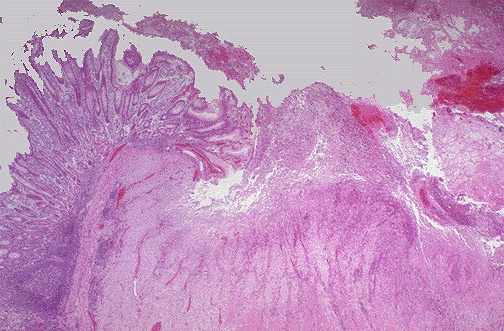

Correlation 9: Peptic ulcer diseaseNote the normal gastric epithelium, at the left while there is loss of the epithelium over the area of ulceration. Loss of epithelium in a localized area is called ulceration. The protection afforded by the epithelium is lost. A good example of this occurs in the upper gastrointestinal tract in the form of peptic ulcer disease involving the stomach and duodenum. These ulcers result from the presence of acid secreted by the mucosa of the stomach. The normal epithelium is designed to resist this acid, principally because of the mucus that is secreted over the surface of the epithelium by cells in the mucosa that produce mucus. One predisposing factor for peptic ulcers is the presence of an infection with the organism called Helicobacter pylori. This little bacterium grows happily in the overlying gastric mucus and, by itself, does not cause any damage. However, the growth of the H. pylori organisms changes the physiology of the epithelium to make it function less effectively so that ulcers can occur. Billions of dollars are spent each year in the U.S. on drugs that can either reduce acid secretion or inhibit growth of H. pylori. Any normal epithelium is normally replacing itself in days to weeks, so epithelial surfaces have the capacity to easily regrow, which is a good thing. Inhibiting the causes for peptic ulcers allows the epithelium to regrow and heal the ulcer. |